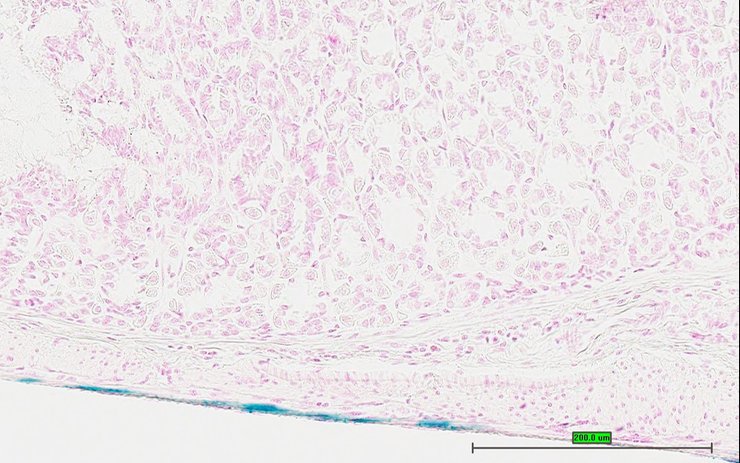

Assay type: In situ reporter (knock in)

Gene symbol: Npr3

Gene name: natriuretic peptide receptor 3

Reporter: lacZ

Specimen UC Davis_1885047: postnatal adult; Npr3tm1.1(KOMP)Vlcg/Npr3+ (more )

Structure Level Pattern Image Note

TS28: esophagus Present UC Davis_1885047